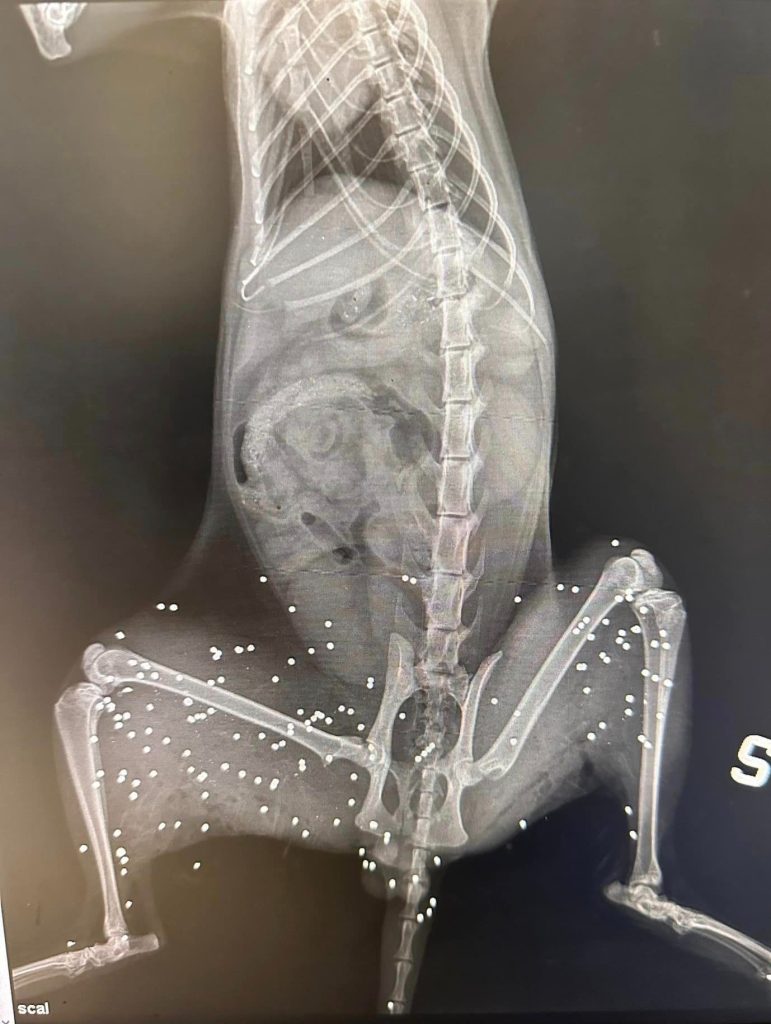

Itri: colpisce il gatto probabilmente con un fucile, forse come passatempo – “Ad Itri in Zona Cappuccini/via Cescole, nei pressi della salita Mezzabrino è stato ritrovato un gatto sparato in pieno paese, probabilmente con un fucile da caccia (dicono un solo colpo, a rosa larga, di quelli che si usano per cacciare gli uccellini). Ennesimo caso di crudeltà nei confronti di un essere indifeso. Sembra ormai essere all’ordine del giorno praticare la violenza come passatempo. Chiunque abbia visto qualcosa, PARLI. Tutto questo è grave ed inaccettabile. Il responsabile di questo abominio deve pagare.” Questo è lo sfogo di un utente sui social che ha deciso di rendere pubbliche anche le foto del gatto per far comprendere la crudeltà del gesto. Di seguito le immagini: